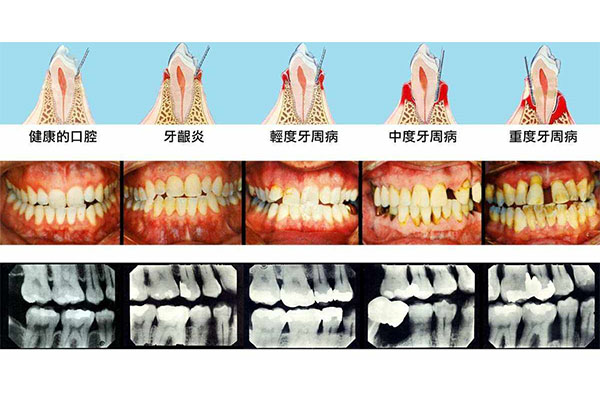

温馨提示:口腔出现问题,需要及时修复,不然会导致问题越来越严重,如果您有这方面的需求,您可以联系我:135XXXXXXXX(点击电话即可复制),或者在下方在线留言。